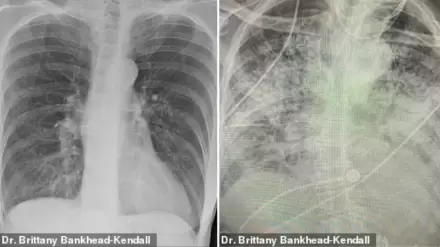

Доцент Центра медицинских наук Техасского технологического университета, доктор Бриттани Бэнкхед-Кендалл показала три рентгеновских снимка легких: здорового человека, курильщика и пациента с коронавирусом.

По словам хирурга, легкие выздоровевших пациентов с COVID-19 выглядят намного хуже, чем у курильщиков. Снимок выглядел почти полностью белым. Врач пояснила, что помутнение легких обычно указывает на то, что они наполнены такими веществами, как жидкость или бактерии, а также плотными рубцами и повреждениями.

У курильщика они частично побелели от рубцов, и снимок выглядит слегка туманным.

На рентгеновском снимке здорового пациента много черного пространства, что является показателем нормального количества кислорода.

"Легкие после коронавируса выглядят хуже, чем любые ужасные легкие курильщика, которые мы когда-либо видели. И они разрушаются", - заявила она.

По ее словам, многие эксперты в области здравоохранения концентрируют внимание на показателях смертности, а не на долгосрочных последствиях выживших. Доктор Бэнкхед-Кендалл также отметила, что почти у всех пациентов из тех, кого она лечила, и тех, кто переболел коронавирусом, был плохой рентген грудной клетки.

Врач добавила, что коронавирус часто приводит к таким осложнениям, как пневмония, которая возникает при наполнении легких жидкостью. Поскольку воздушные мешочки наполняются жидкостью, они не могут принимать достаточно кислорода и воспаляются, что приводит к таким симптомам, как кашель и одышка. Она подчеркнула, что если человек все еще испытывает одышку после выздоровления от COVID-19, то ему стоит немедленно обратиться к врачу первичной медицинской помощи.